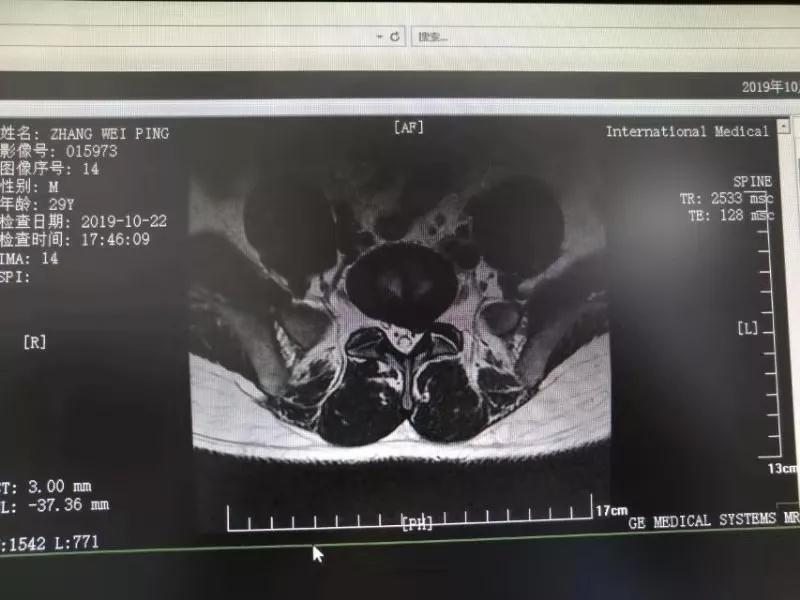

10月25日,29歲的患者小張了解到西安國際醫(yī)學(xué)中心骨科醫(yī)院專家云集,一大早便在家人的陪同下,來到西安國際醫(yī)學(xué)中心骨科醫(yī)院就診。“我腰痛持續(xù)2年多,最近感冒后腰痛癥狀明顯加重了?!毙埫媛犊喑?,因?yàn)殚L期腰痛、左下肢放射性疼痛,她晚上睡覺不能平躺,經(jīng)常疼得睡不著,需要口服止痛藥物才能有所緩解。走路走不了多遠(yuǎn)就開始腿抽的疼,嚴(yán)重影響到工作和生活。

結(jié)合患者的檢查以及年齡情況,王自立副院長推薦讓專門研究椎間孔鏡技術(shù)王雄勛主任給小張做微創(chuàng)的椎間孔鏡手術(shù)。該手術(shù)創(chuàng)傷很小,不影響脊柱的穩(wěn)定性,尤其適合于椎間盤突出的年輕患者,懷著對骨科醫(yī)院專家的信任,小張與家人商議后,接受手術(shù)治療。